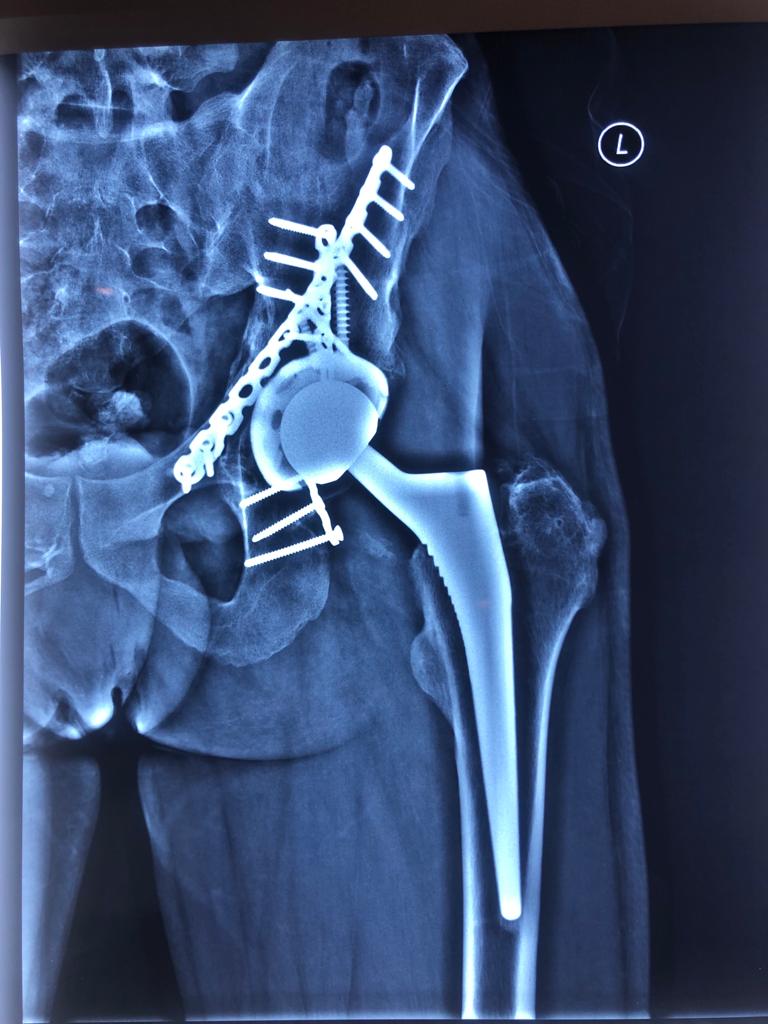

Revision Total Hip Arthroplasty Femoral Stem